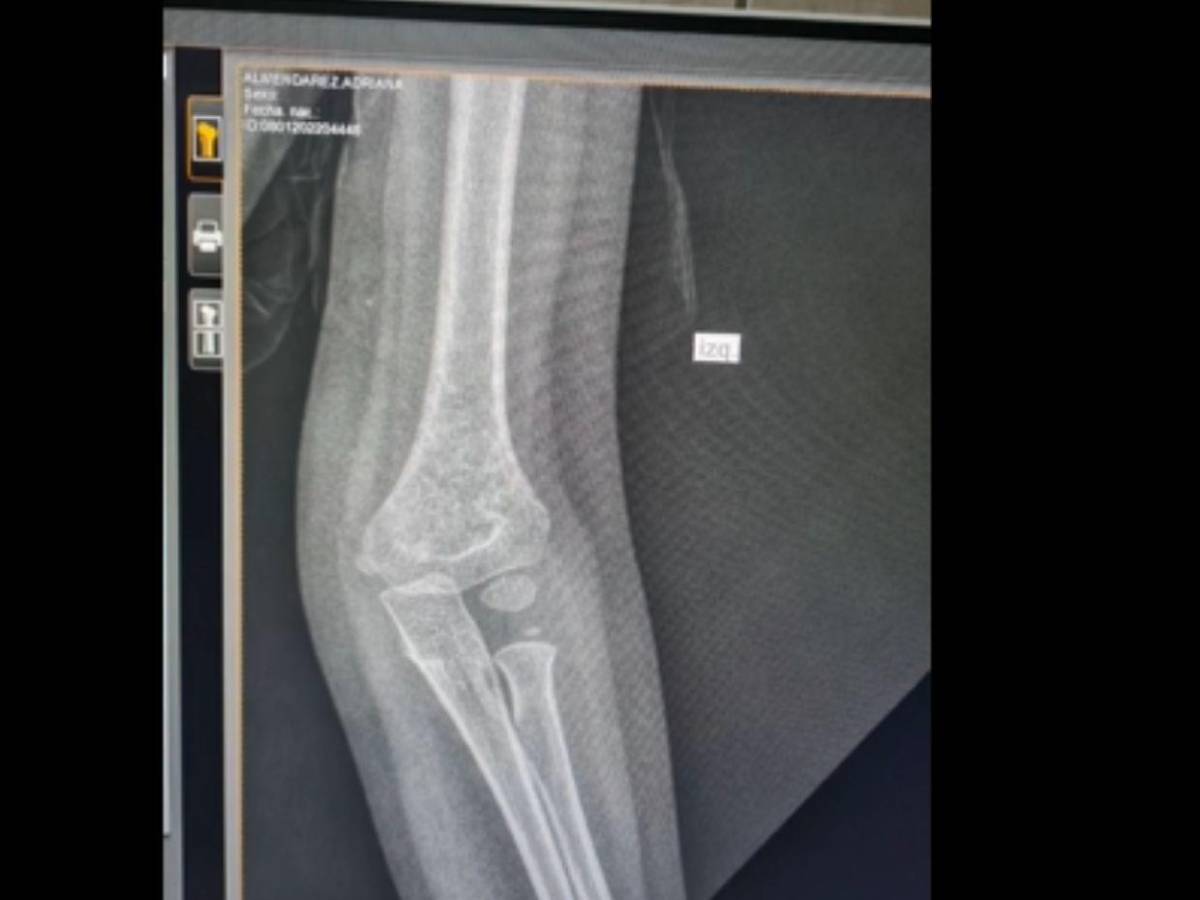

“Mi hija se cayó y se fracturó el codo. El papá la llevó al Seguro y yo llegué después, luego de salir de trabajar. Fuimos a hacerle las radiografías, pero nos dijeron que continúan sin placas”, expresó la comunicadora.

Agregó, con evidente indignación, que “uno tiene que tomarle una foto al examen con el teléfono para luego mostrársela al doctor”.

Según relató, los médicos también se mostraron inconformes con tener que revisar las radiografías a través de fotografías en un celular.

“El mismo doctor me dijo que no podían seguir así, porque eso puede provocar errores, ya que no se observan claramente las radiografías”, afirmó Espinal.